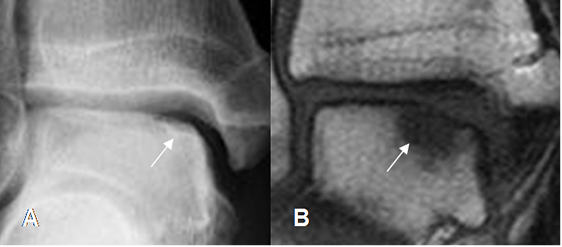

Fig 40. Lesión osteocondral estado III

A: Rx AP y B: RM coronal en STIR. Fragmento desprendido, pero no desplazado.